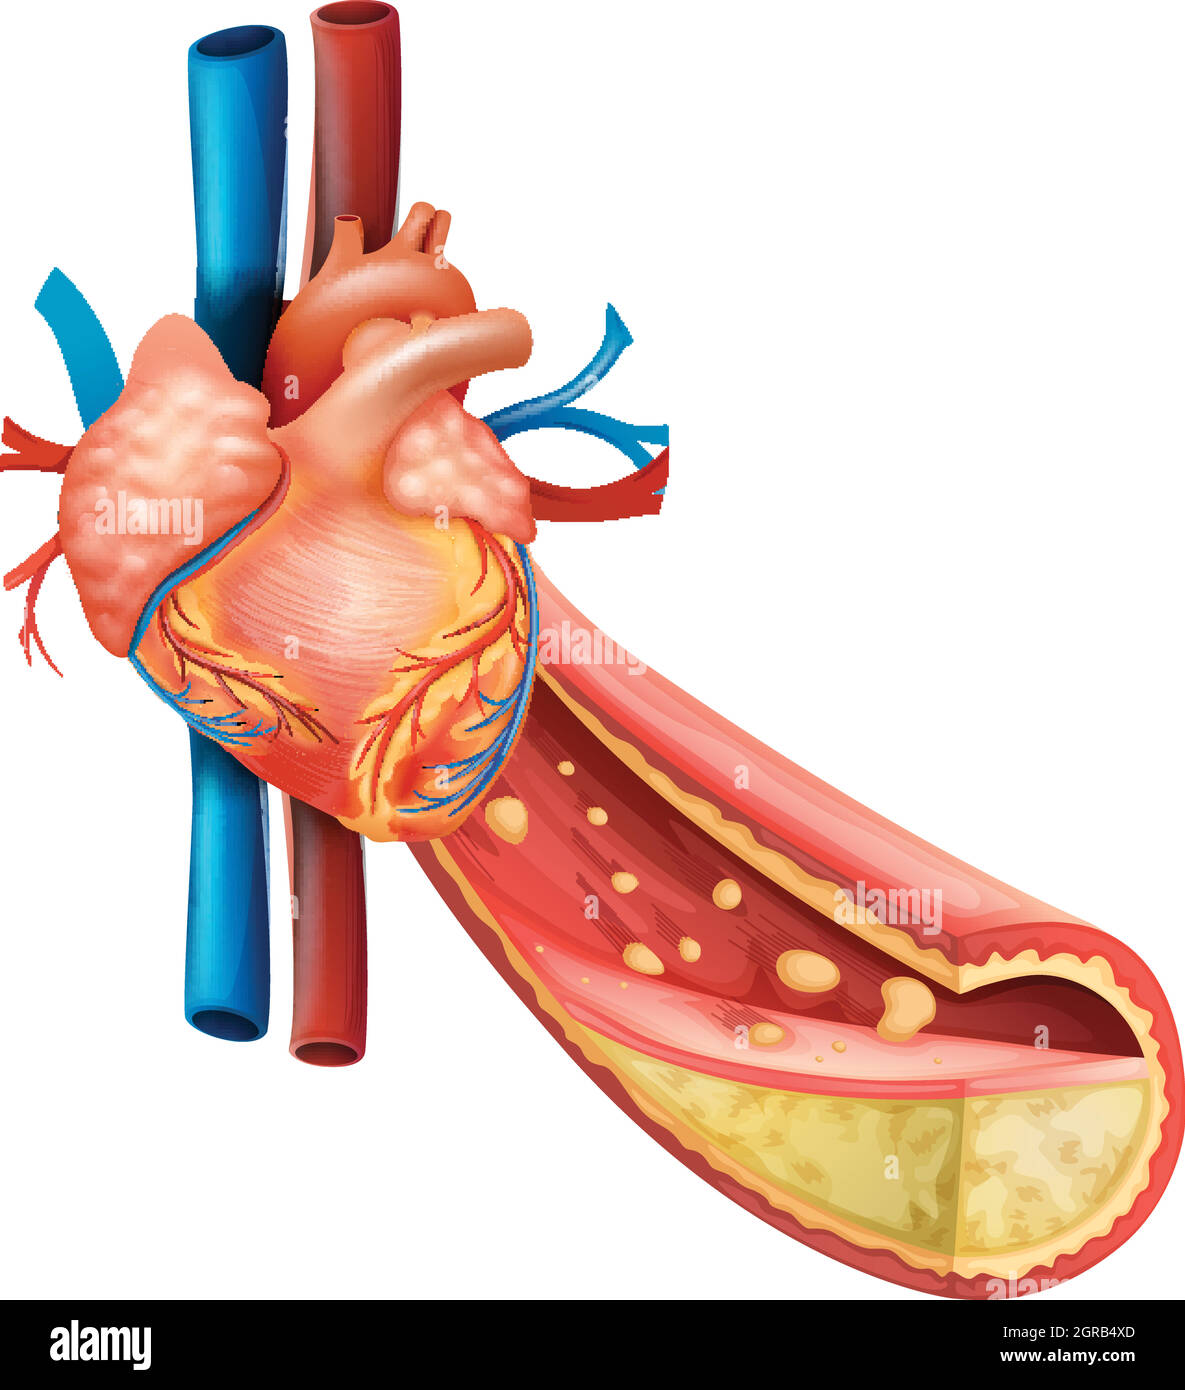

Diagram showing human heart and fat veins Stock Vectorhttps://www.alamy.com/image-license-details/?v=1https://www.alamy.com/diagram-showing-human-heart-and-fat-veins-image444641637.html

Diagram showing human heart and fat veins Stock Vectorhttps://www.alamy.com/image-license-details/?v=1https://www.alamy.com/diagram-showing-human-heart-and-fat-veins-image444641637.htmlRF2GRB4XD–Diagram showing human heart and fat veins